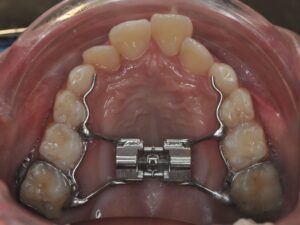

L'AXE ORTHOPÉDIQUE

Il correspond à la réorientation des croissances des mâchoires supérieures et inférieures. En effet, tant que l’enfant est encore jeune, la croissance peut être déverrouillées, voire guidée afin qu’une croissance harmonieuse des mâchoires se fasse.

Il s’agit de la mastication, la respiration, la posture linguale, les habitudes déformantes. Elles font partie intégrante de la bonne posture des mâchoires et des dents. Elles seront également contrôlées et interceptées. Les appareils sont nombreux en fonction de la malocclusion, ils peuvent être fixes ou amovibles. Très souvent, l’interception pourra être associée à un rendez-vous chez : l'ORL, l'orthophoniste, le kinésithérapeute ou encore l'osthéopathe.